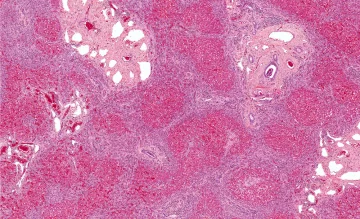

Компанія ISCO, що спеціалізується у сфері біомедицини та застосування стовбурових клітин в терапії, розробила новий біопрінтер, оптимізований для тривимірної друку печінкових клітин-попередників. З цих клітин, здатних диференціюватися в холангіоцити, гепатоцити і зірчасті клітини, тепер можна друкувати тканини, що нагадують за структурою печінку. А вони, в свою чергу, придатні для імплантації в пошкоджену печінку або для проведення на них випробувань нових медичних препаратів.

Клітини-попередники можуть друкуватися з будь-якого стволового матеріалу. Навіть з зародкових клітин людини. Це дасть можливість заповнити дефіцит донорської печінки. В одних тільки США в черзі на трансплантацію стоять 17 тисяч осіб. Лише третина з них щорічно отримує необхідний матеріал.